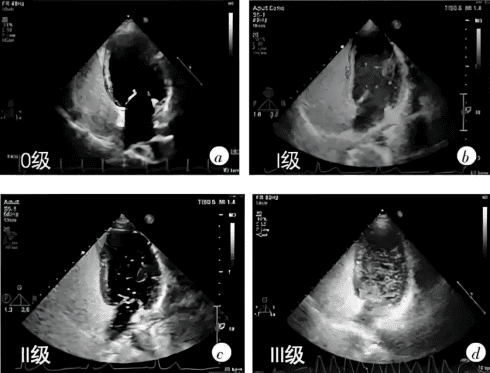

心脏组拥有多台目前世界上先进的大型彩色超声诊断仪,开展了常规心脏超声心动图、经食管超声心动图、三维超声心动图、超声引导下介入治疗和术中监测等多项检查,诊断经验丰富,技术力量雄厚。

心脏超声:

①常规二维及三维经胸超声心动图 ②经食管三维超声心动图 ③右心声学造影(发泡试验) ④左心及心肌超声造影 ⑤胎儿三维超声心动图